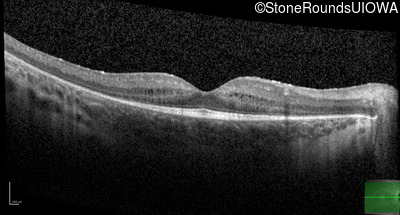

Age at visit: 11 years